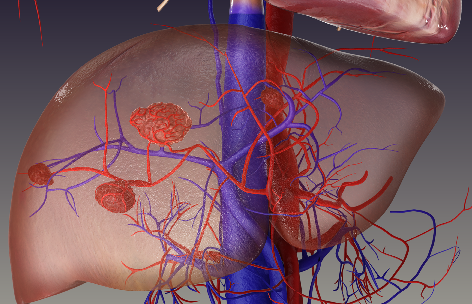

The organ in which a cancer originated is called the "primary cancer site", and this site gives cancer its name, like liver cancer or colorectal cancer.

Cancer that has spread from the primary site to another organ (e.g, the liver or lungs) is called metastatic or secondary cancer.